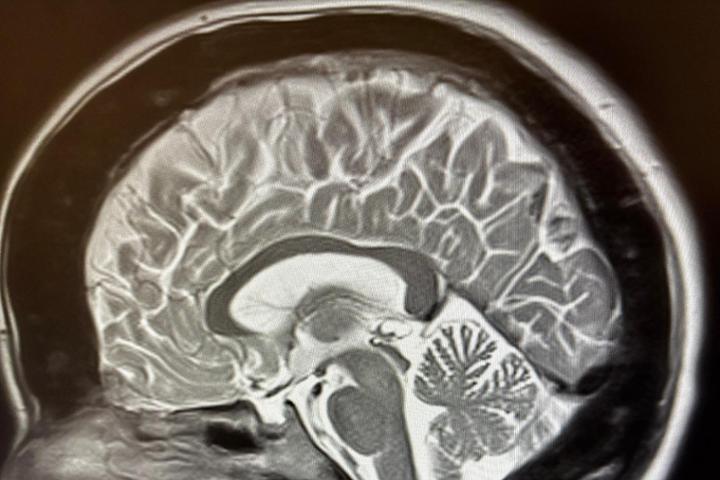

Nuestro proyecto es conseguir una vía de investigación que sepa por que los huesos no nos dejan de calcificar. Esta investigación es muy importante ya que nos puede ayudar a entender por que el cuerpo calcifica o descalcifica y por que lo hace. Hasta ahora se sabe poco o nada de por que nosotros con el paso del Tiempo seguimos calcificando. Nuestro problema surge cuando nos afecta a nervios y nos quita movilidad. Llegando en algunos caso a producir parálisis, sordera e insensibilidad.